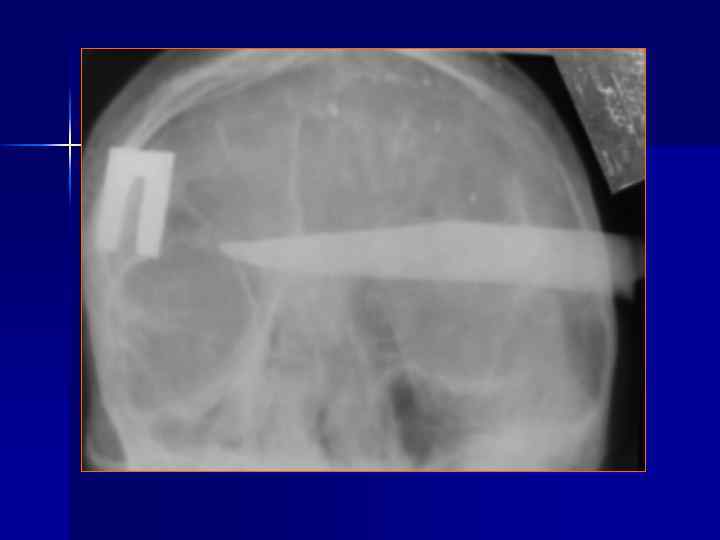

Переломы костей свода черепа N. B. -1/3 больных с тяжелой ЧМТ не имеют переломов костей. Выделяют: Линейные Вдавленные Расхождение швов Дырчатые Огнестрельные Наиболее информативна КТ, позволяющая одновременно оценить костные и внутримозговые повреждения.